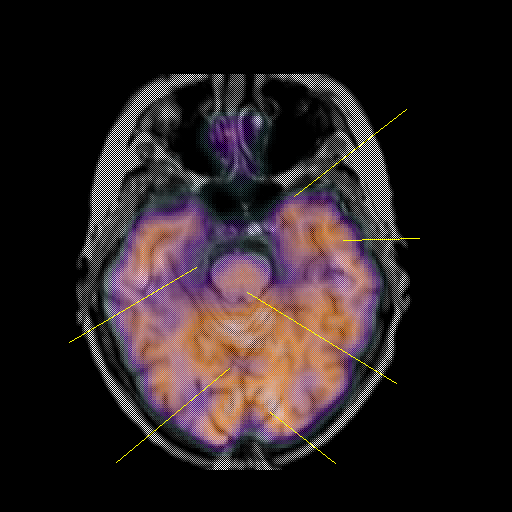

overlay: Slice 18

Slice 18

MRCBFCBF with

Unlabeled

Pointers

Labeled